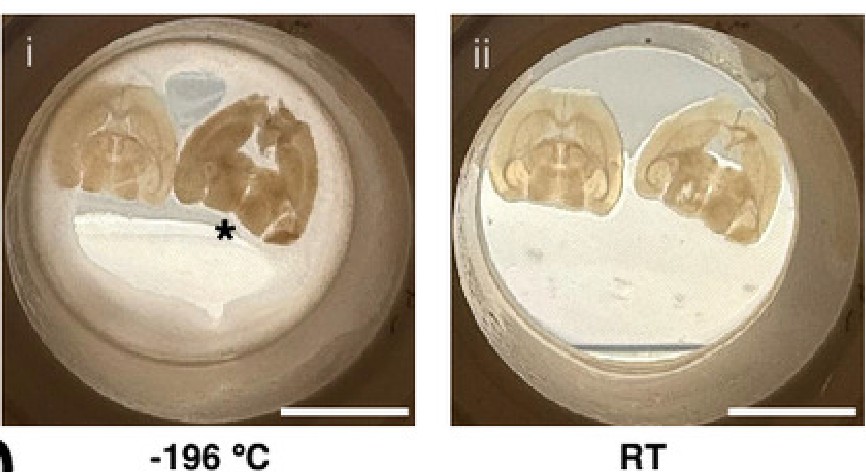

まず、マウスの脳を薄くスライスした切片での試験が行われた。液体窒素でマイナス196度に冷却された銅製シリンダーの上に置いてガラス化凍結させた後、切片はマイナス150度の液体窒素中で10分から7日間保存され、その後に解凍された。ガラス化溶液(凍結防止剤)の配合を微調整することで、研究チームは水分の結晶化を完全に回避することに成功した。

ガラス化凍結されたマウスの脳はマイナス140度で1~8日間保存された後に解凍され、溶液が洗い流された。しかし成功率は芳しくなく、3回のうち生理学的評価に適した組織が得られたのは1回だけだったという。